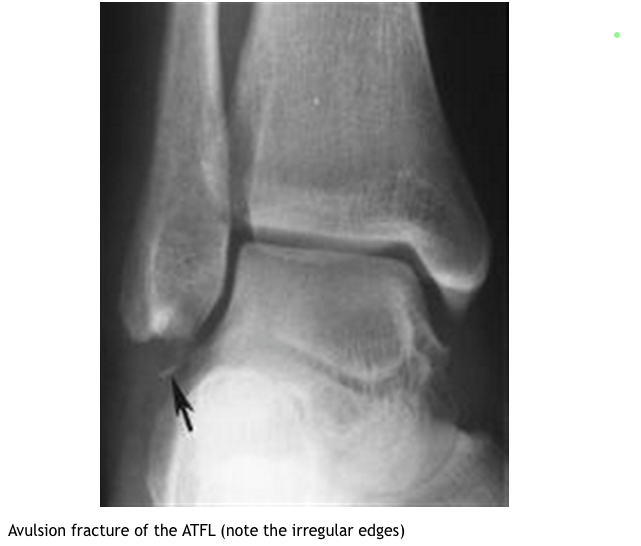

What imaging is helpful in Os Subfibulare?

What is DDX of Os Subfibulare?